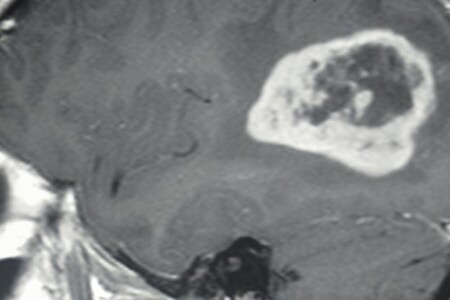

Glioblastom je nejzhoubnější mozkový nádor, který vzniká z gliových buněk. Glioblastom má různorodé projevy, kdy se setkáváme s bolestí hlavy, nevolností, zvracením, ale i změnami psychiky, či epileptickými záchvaty. Glioblastom se pro svou neohraničitelnost a nepravidelnost nedá stoprocentně vyoperovat a špatně reaguje na ostatní léčebné metody. Proto je prognóza glioblastomu velmi špatná.